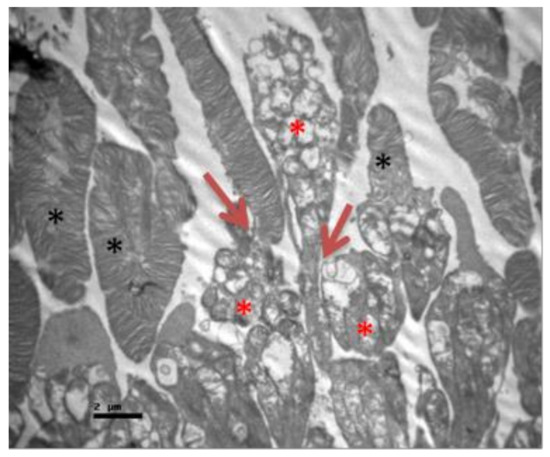

2.1. Group C

2.2. Group V

2.3. Group M